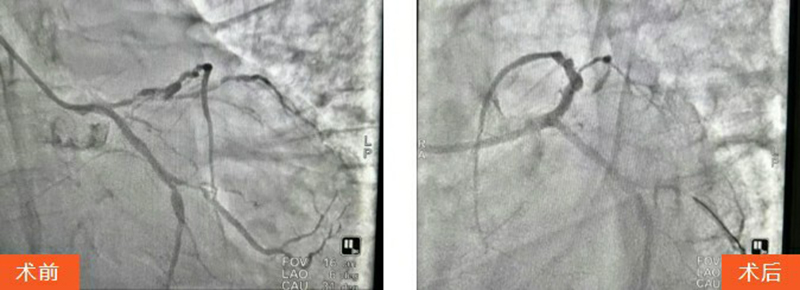

王先生被迅速送往血管介入科行急診PCI(經(jīng)皮冠狀動(dòng)脈介入治療)。術(shù)中,馬建亮主任帶領(lǐng)心血管內(nèi)科專家團(tuán)隊(duì)為其進(jìn)行血管造影檢查,結(jié)果顯示:冠脈三支血管病變,前降支彌漫性病變伴鈣化,次全閉塞累及主干,病情極其兇險(xiǎn)。

手術(shù)過程中患者生命體征不穩(wěn)且煩躁不安,血管介入科團(tuán)隊(duì)全程安撫配合,馬建亮主任團(tuán)隊(duì)果斷采用球囊擴(kuò)張病變血管,成功植入2枚冠脈支架,最終使患者轉(zhuǎn)危為安。